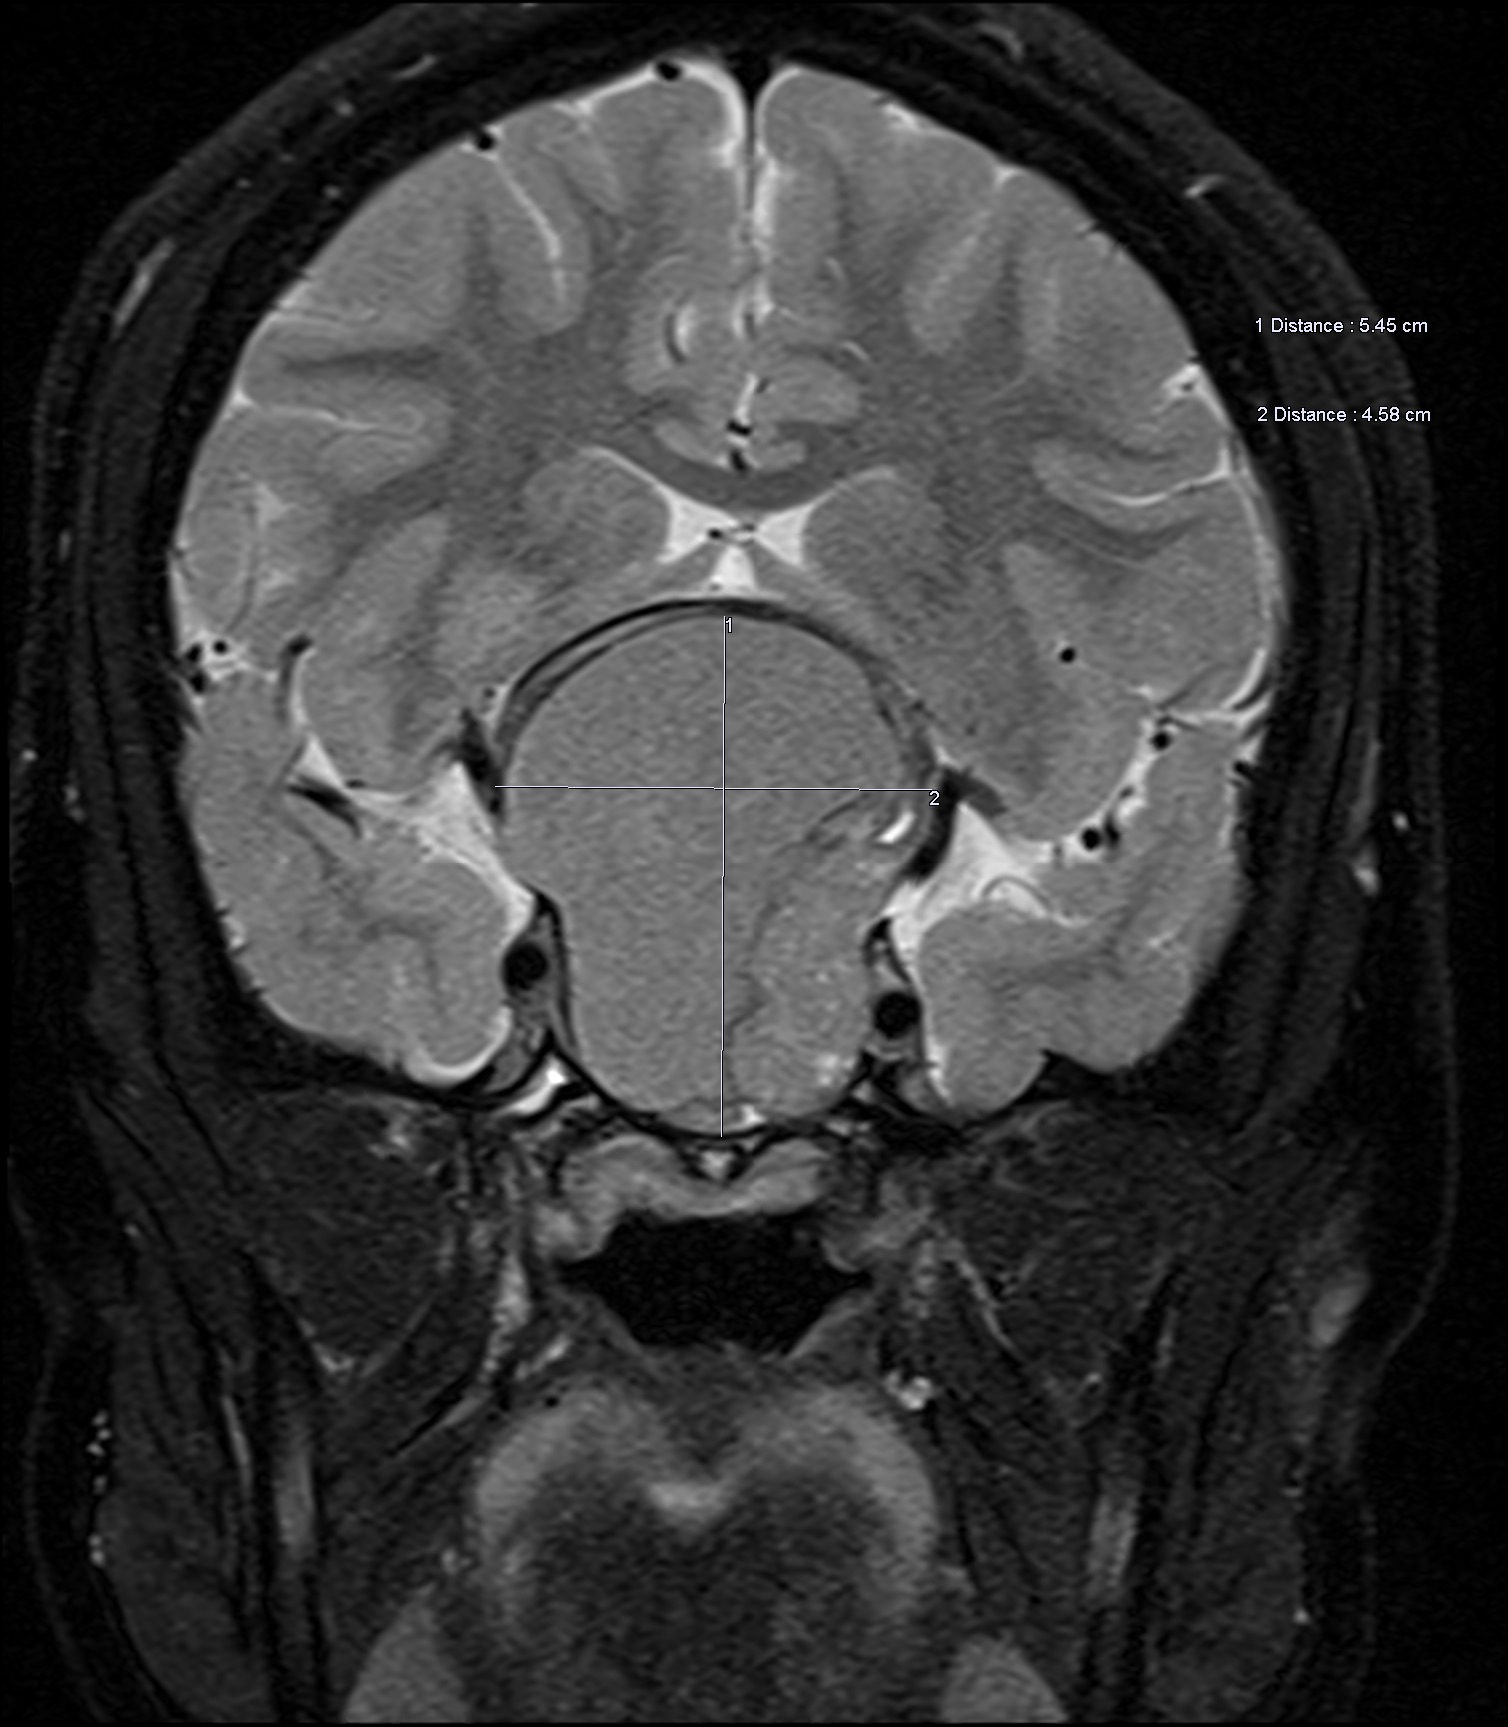

MRI results revealed a 5.5-cm solid and cystic mass with multiple fluid levels in the sellar and suprasellar areas, displacing and compressing the optic nerves and optic chiasm (Figures 1-3).

Figure 3. Coronal T2-weighted image showing expansion of the sella and displacement of optic nerves superiorly.